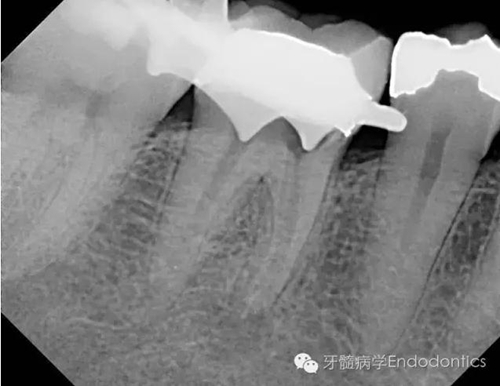

患者因右下第一前磨牙劇烈疼痛、腫脹來診,自訴2年前該牙行根管治療,突發(fā)劇痛。X線示患牙已行根管治療并超填?;佳涝\斷為已行根管治療合并急性根尖周膿腫。一些牙醫(yī)和牙髓病專科可能會直接采取根尖手術(shù)治療患牙,而我認(rèn)為手術(shù)是最終手段,尤其對于該病例。

圖1.術(shù)前X線片(a)